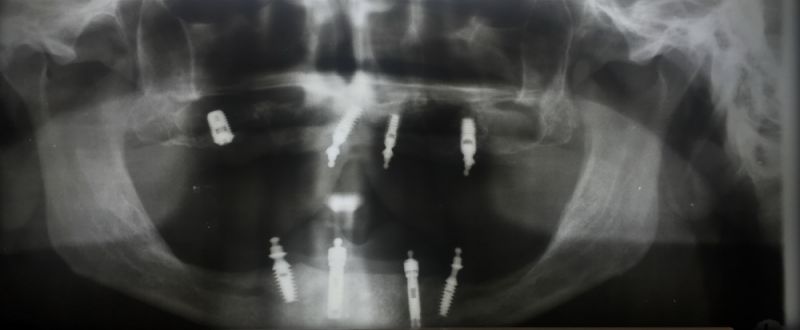

Viele Jahre haben die Implantate gehalten

Nun musste aber ein Implantat in regio 16 entfernt werden, wegen einer Periimplantitis.

Das Implantat und auch alle anderen wurden in 2003 gesetzt und war seitdem in Funktion. Alle anderen sind es immer noch! Seit inzwischen über 12 Jahren.

Das Schöne an der bestehenden Rekonstruktion: Das Implantat konnt entfertn werden, die vorhandene Prothese in der Zeit der Wundheilung weiterg etragen werden, auch als ein neues Implantat unter die bestehende Prothese neu inseriert wurde.

Diese neue Implantat wurde heute in der Praxis, man nennt es "chairside" in die bestehende Prothese eingebunden.

Nach 9-jähriger Nutzungszeit werden die beiden O-Ring-gestützten Totalprothesen im nächsten

Jahr erneuert.